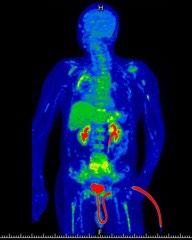

PETCT: interval reduction in metabolic activity at diffusely intense FDG uptake involving the axial and appendicular bones - good partial response

• PET CT after 6 months of teclistamab (1/2024)

• previous R NP mass, cervical LN, R hilar mass, peritoneal mass, peritoneal deposit, paraspinal soft tissue mass, epidural mass from T9-11 resolved